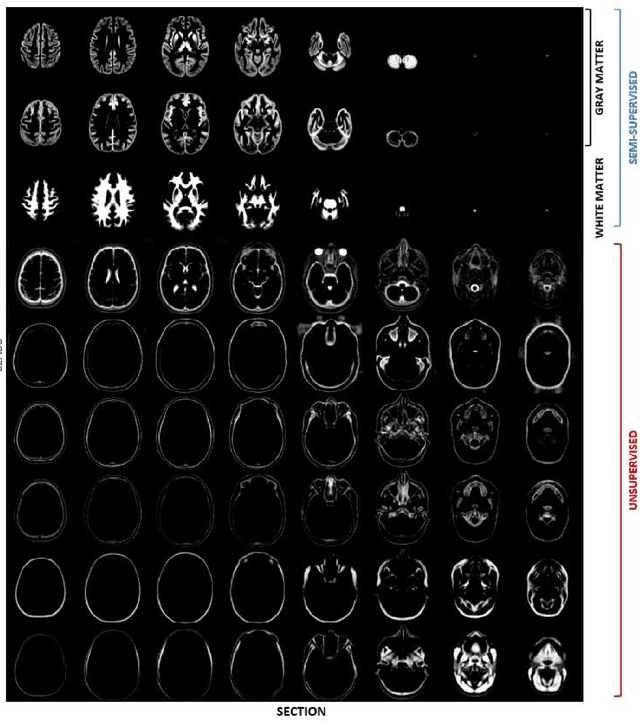

Abstract:In this paper we will focus on the potential and on the challenges associated with the development of an integrated brain and spinal cord modelling framework for processing MR neuroimaging data. The aim of the work is to explore how a hierarchical generative model of imaging data, which captures simultaneously the distribution of signal intensities and the variability of anatomical shapes across a large population of subjects, can serve to quantitatively investigate, in vivo, the morphology of the central nervous system (CNS). In fact, the generality of the proposed Bayesian approach, which extends the hierarchical structure of the segmentation method implemented in the SPM software, allows processing simultaneously information relative to different compartments of the CNS, namely the brain and the spinal cord, without having to resort to organ specific solutions (e.g. tools optimised only for the brain, or only for the spinal cord), which are inevitably harder to integrate and generalise.